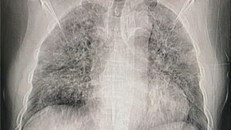

Hình ảnh phổi người mắc Covid-19 ở Việt Nam

Khi chưa xét nghiệm rRT-PCR hoặc kết quả âm tính, bác sĩ vẫn có thể kết luận bệnh nhân mắc Covid-19 dựa vào những tổn thương ở phổi.